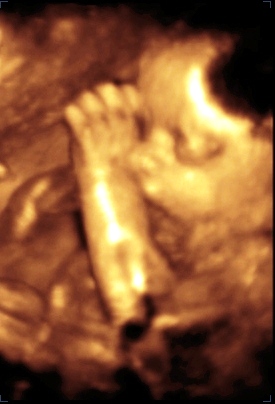

Voltunk szombaton Veszprémben 4 D-s uh-on. A tesónak szinte minden mérete pont megfelelő, ill. 1-2 nap eltérés van. Kb. 1250 gr lehetett akkor, és ha így folytatja a növekedést, kb. 3 és fél kilós lesz (persze, ha bent marad a 40. hétig). Nem bánnám, ha vagy hamarabb kibújna, vagy visszavenne egy kicsit a tempóból, mert Máté is 3500 gr-mal született és akkor most is császár lenne ...

Íme a kistesó:

Kép Kép